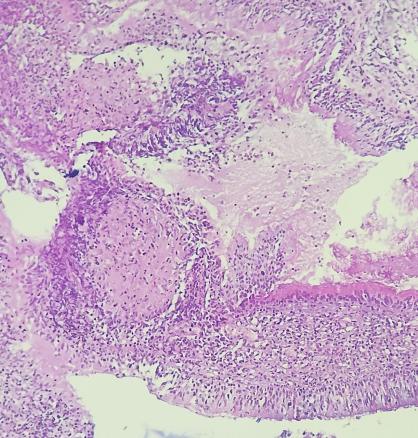

Une patiente âgée de 40 ans est admise à l’hôpital pour exploration d’adénopathies cervicales. L’interrogatoire révèle une obstruction nasale chronique accompagnée d’une rhinorrhée. L’endoscopie met en évidence une rhinite croûteuse avec un bombement du cavum (fig. 1). La tomodensitométrie montre un cavum pseudotumoral (fig. 2, 3 et 4). L’histologie objective un processus granulomateux tuberculoïde (fig. 5). Le GeneXpert sur fragment de biopsie, l’intradermoréaction à la tuberculine et la recherche de bacille de Koch dans les crachats sont négatifs.